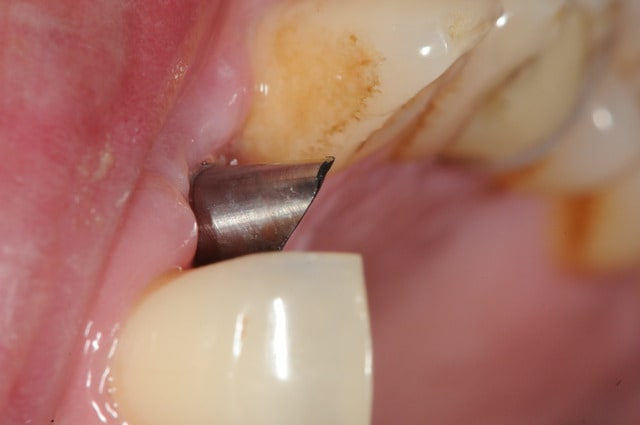

sinon, tu peux toujours partir d'un pilier standard et tu fait une provisoire dessus qui s'adapte au mieux...

comme olivier tu en sacrifies une vingtaine, mais bon, c'est pas grave tu peux t'en re-servir.

ici, c'est un implant AXIOM, le diamètre à la sortie du col de l'implant est très fin (cône et platform switching) et permet donc de travailler l'émergence au mieux.

je dis cela car sur les autres type d'implants avec une connexion plate, l'utilisation d'un pilier personnalisé est plus souvent nécessaire.